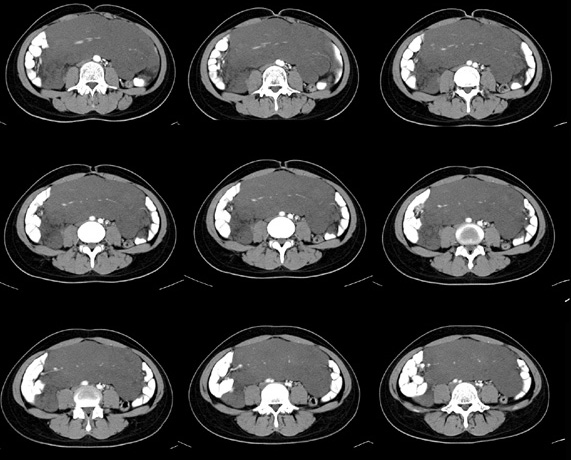

女性,28岁,停经3月,腹部膨隆1月,产前检查发现腹部占位

{肿块中心ct值27hu,增强后,动脉期、门脉期均无明显强化)

继续发

患者手术病理:腹腔囊性淋巴管瘤,象这样充满整个腹腔的的确很少见